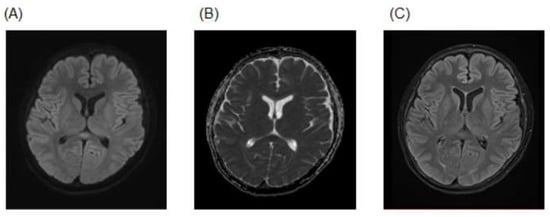

2. Case Presentation

| This Case | MERS | 18/m | Orthostatic hypotension | Confusion | Yes | No | No | 128.9 mEq/L | Normal | High | Low | High | Follow-up MRI (11 days): complete regression of the corpus callosum lesion | No | Remdesivir | Recovery |